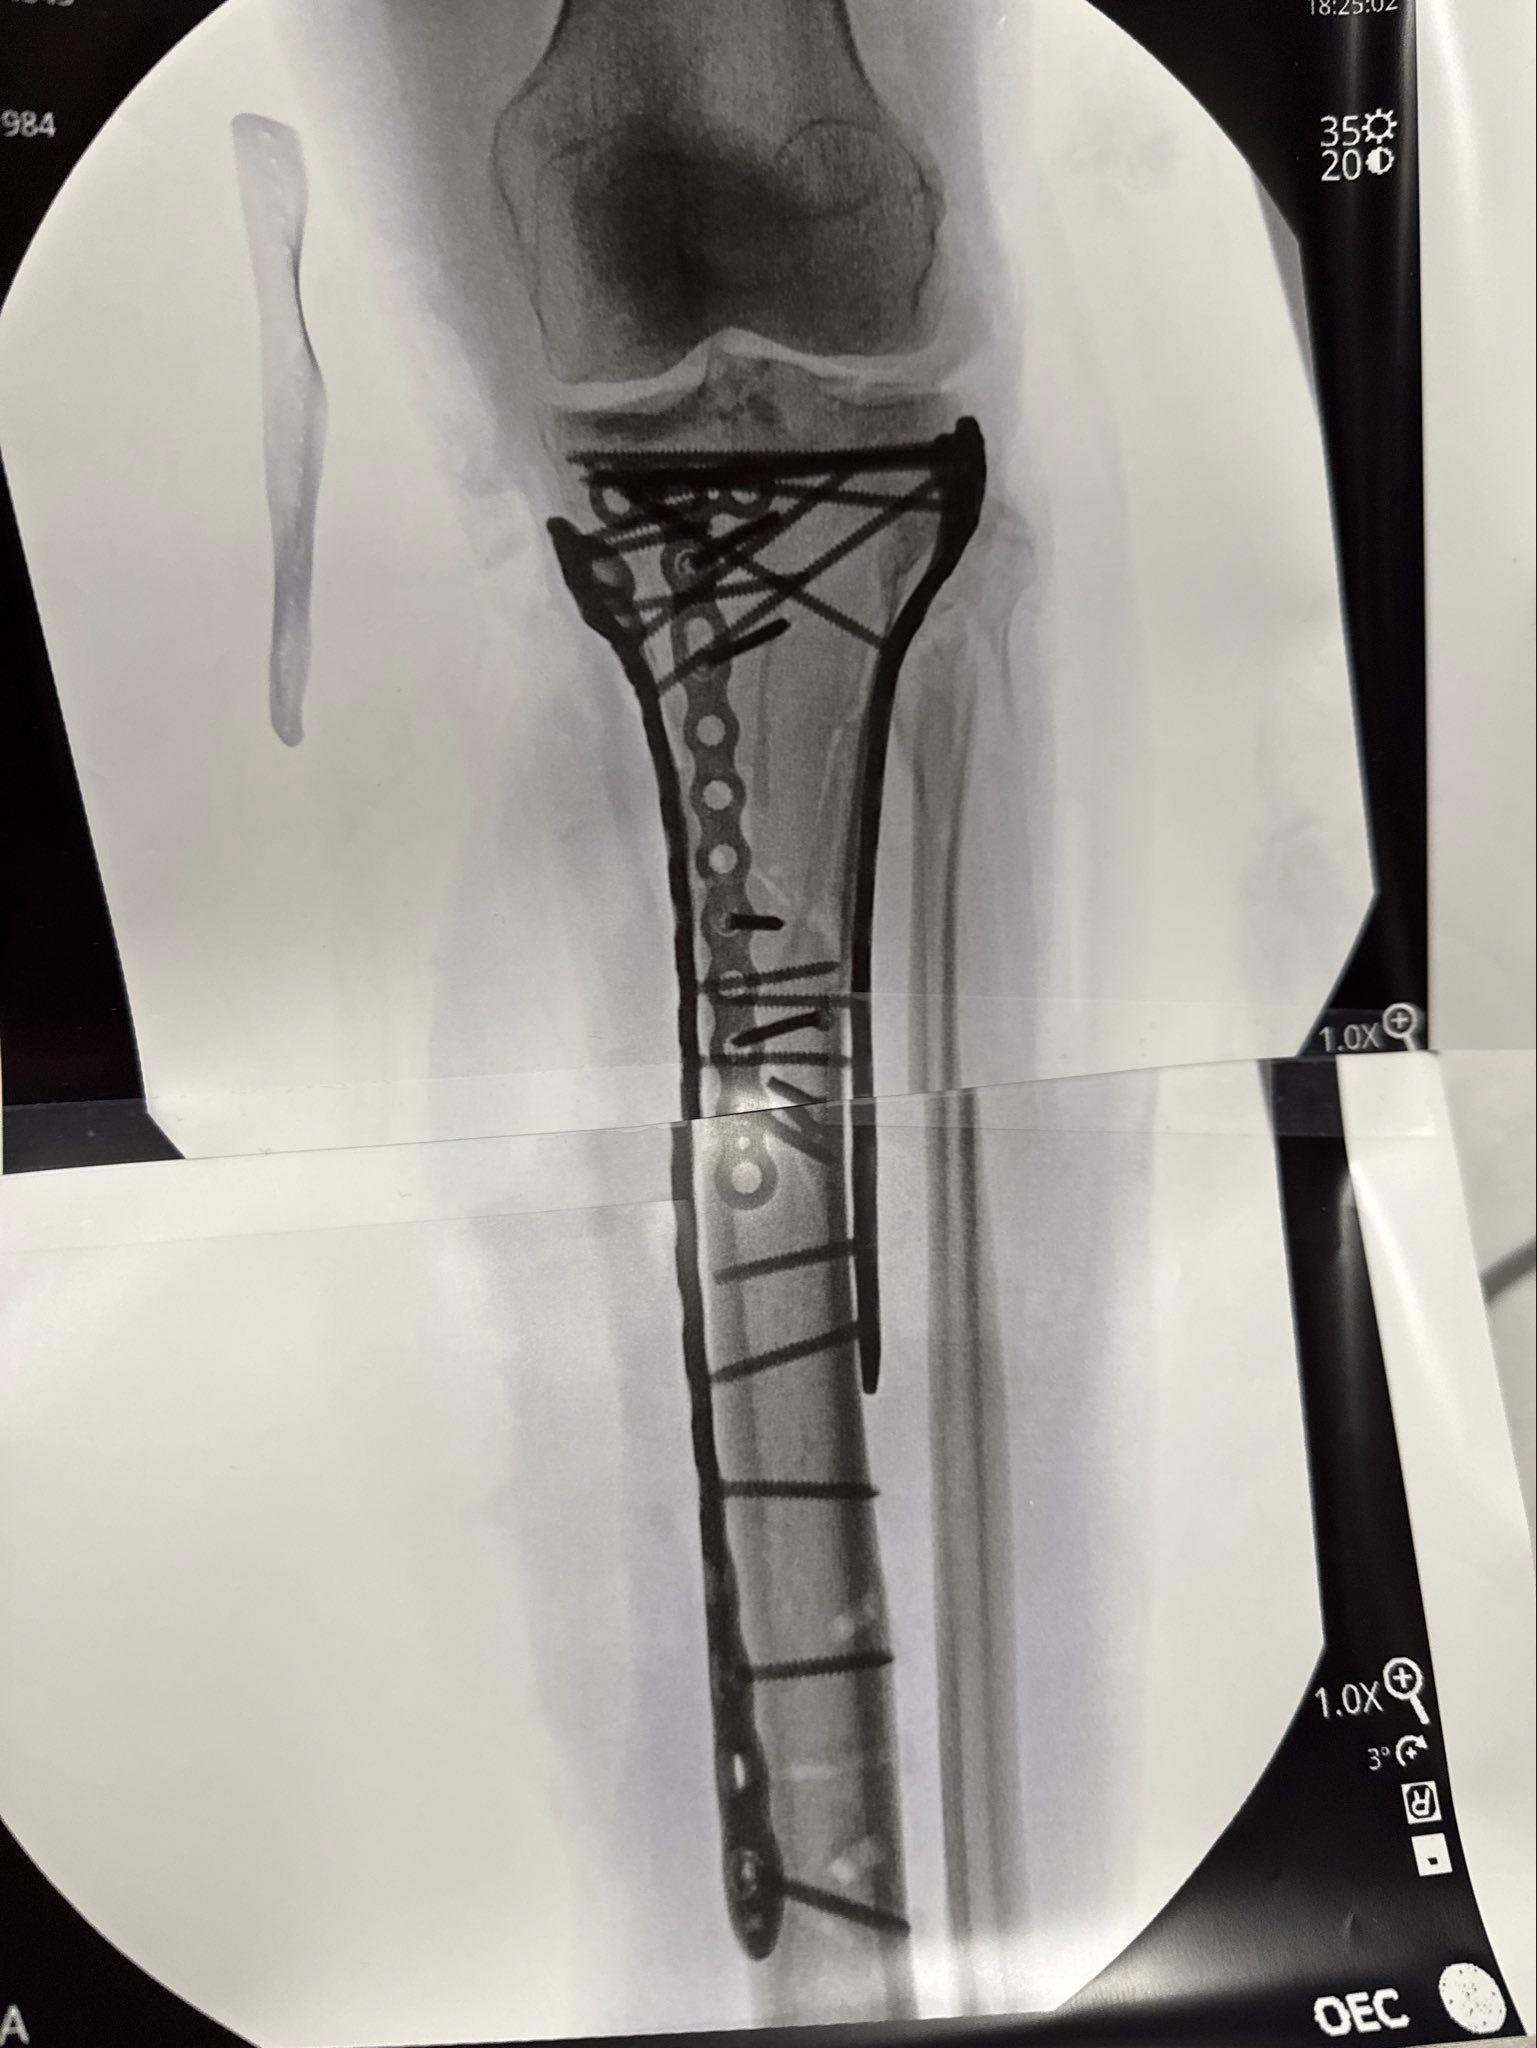

Jedna od najboljih skijašica svih vremena, Amerikanka Lindzi Von izjavila je da je umalo ostala bez noge posle teškog pada na Zimskim olimpijskim igrama u Italiji i zahvalila se lekaru koji ju je spasao od amputacije.

Skijaška zvezda je imala šest operacija otkako je slomila nogu i skočni zglob u ženskom spustu u Italiji 8. februara.

Noga mi je bila „u komadima“, rekla je.

Imala sam sindrom kompartmenta, pritisak unutar mišića, koji ograničava protok krvi, a hirurg me je hitno operisao kako bi ublažio pritisak, dodala je.

„Dr Tom Haket mi je spasao nogu - spasao ju je od amputacije.

„Otvorio je obe strane moje noge, tako da je bila otvorena i pustio je da diše, takoreći. Spasio me je“, rekla je 41-godišnja skijašica.

„Onda ću odlučiti da li želim da izvadim sve metale iz noge ili ne, a onda ću ponovo na operaciju zbog prednjih ukrštenih ligamenata (ranije povrede, pre ZOI).“